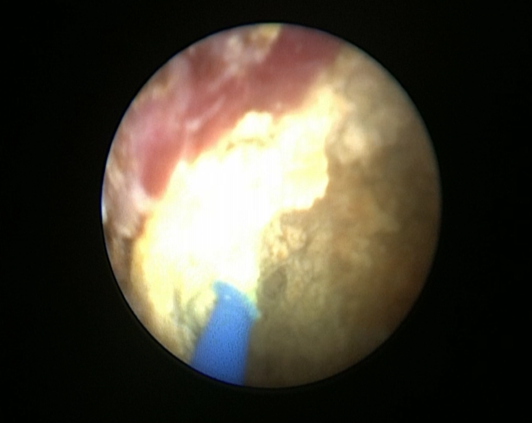

Краткое описание хода операции В полости мочевого пузыря визуализирован фиксированный на дистальном конце внутреннего мочеточникового стента камень, размерами 30х38 мм. С помощью лазерного литотриптора камень фрагментирован, фрагменты отмыты. Извлечен фрагмент внутреннего мочеточникового стента. Под рентгенологическим контролем в левый мочеточник рядом со стентом введен проводник, по проводнику мочеточниковый катетер №7Сh проведен до полостной системы левой почки. В мочевой пузырь установлен катетер Фолея №18.

Пациент перемещен из литотомического положения в положение на спине. Под рентген контролем пунктирована нижняя чашка левой почки. Проводник проведен в лоханку и далее в верхнюю чашку. Установлен страховой проводник. Нефростомический ход поэтапно бужирован Выполнена нефроскопия, при которой определяется камень с желтоватой поверхностью в нижней чашке и лоханке левой почки, размерами 32х34 мм. Камень поэтапно фрагментирован с помощью лазерного литотриптера, фрагменты камня, детрит и внутренний мочеточниковый стент удалены эндоскопическими щипцами через нефростомический ход. Рентген контроль, в ЧЛС левой почки установлена нефростома.